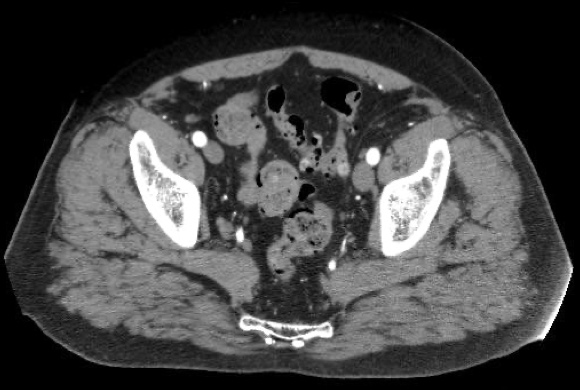

Die Abbildungen zeigten CT und MRT-Scans eines Patienten mit Lymphknotenmetastasen bei einem Prostatakarzinom. Der Patient hatte sich einer Hormonentzugstherapie (ADT Androgen-Deprivations-Therapie) unterzogen, die nicht mehr wirkte. Der PSA-Spiegel war auf 8,65 ng/ml angestiegen. Die Lmyphknotenmetastasen (MRT-Bild rechts oben, Pfeile) sind tief im Becken im Bereich der großen Beckengefäße (Iliakalgefäße) und direkt neben den Ischiasnerven (Nervi ischiadici) lokalisiert. Das Bild rechts oben zeigt die Einbringung der Elektroden in die Lymphknoten im Computertomographen mit Hilfe des infrarotgesteuerten virtual Reality Systems Cascination. Das CT-Bild links unten zeigt die Elektroden in ihrem Verlauf von der Bauchwand bis in die metastasenbefallenen Lymphknoten. Das MRT-Bild rechts unter zeigt das Ergebnis fünf Monate später: Die Lymphknotenmetastasen sind vollständig verschwunden, der PSA-Spiegel sank auf 0,06 ng/ml ab.